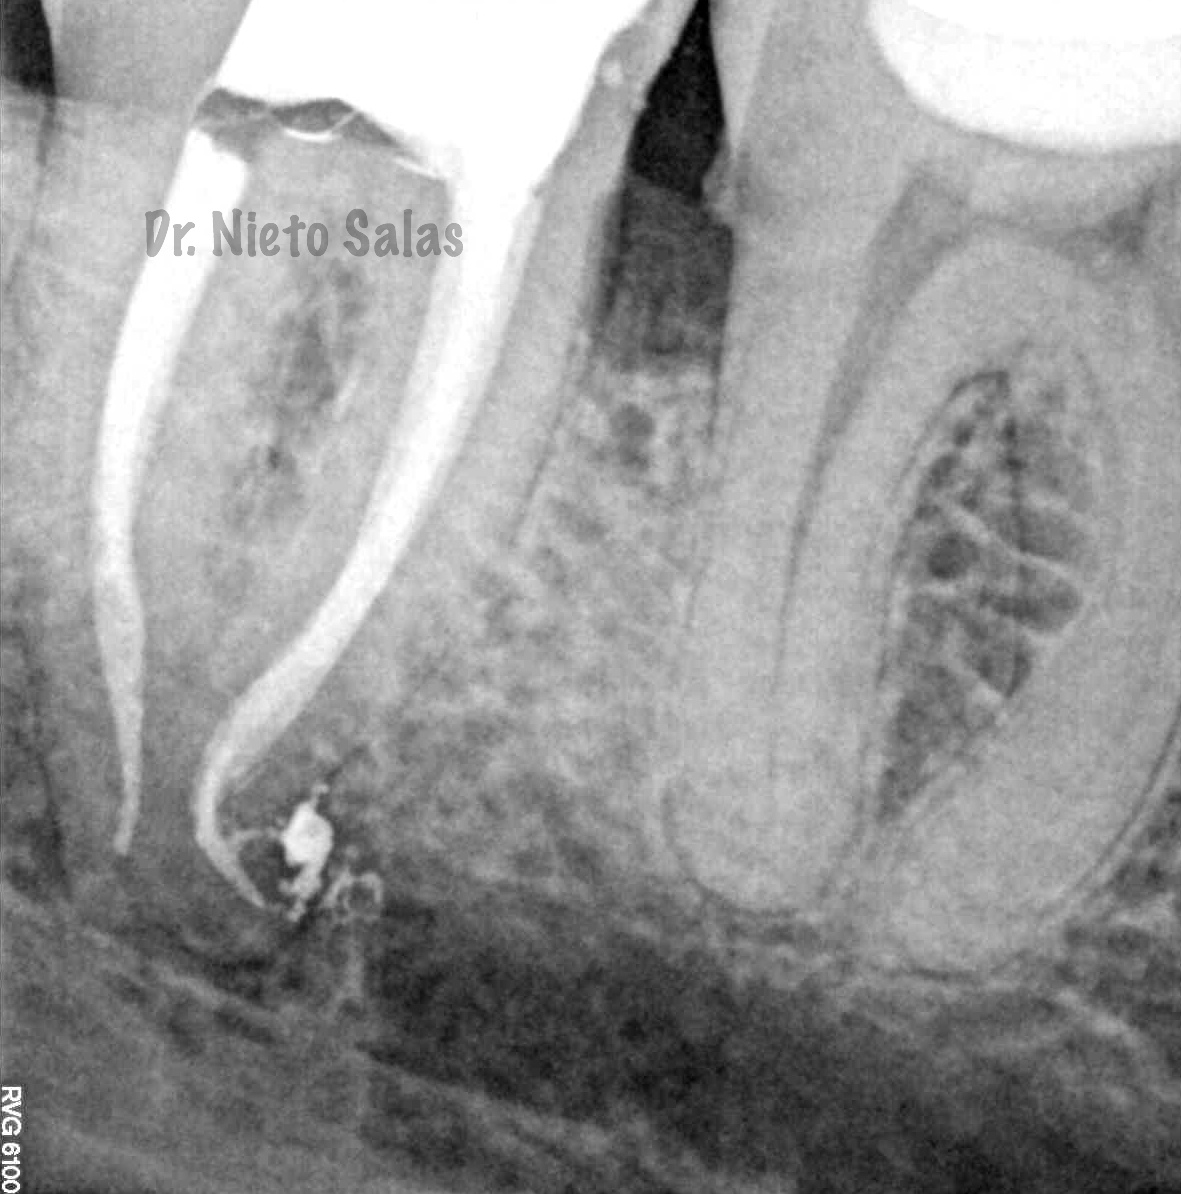

Así pues quedaría el sellado hermético y tridimensional:

La otra pieza, el 3.7, se instrumentó con sistema Protaper y obturación con Ola continua de Calor y un back-filling con la pistola Obtura II.

(buscamos siempre algún conducto lateral, para intentar asegurarnos de su limpieza)

Y una en las demás proyecciones MESIO Y DISTO:

2. disculpe, en las imagenes de la entrada de los conductos, era dos conductos distales o era solo uno ?? muchas gracias y enhorabuena por el casa, es perfecto !!

3. Dr Nieto Salas, en la imagen en que se ven la camara con la entrada de los conductos y la gutapercha, el orificio de entrada en distal era muy ancho, a parte de conductos laterales, localizo un conducto o dos conductos ?? ( la duda es por lo ancho de la entrada). El caso es maravilloso. Le doy mi enhorabuena.

en ese caso en particular, el número de conductos era solamente uno, ya sabes que los conducto distales en muchas ocasiones tienen forma ovalada, con lo que la entrada puede corresponder con las imágenes.